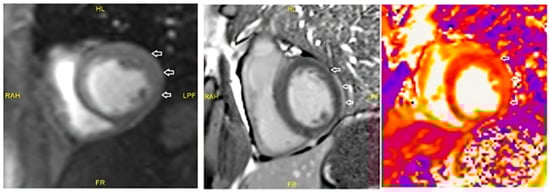

Cardiac MRI findings of Case 3 are shown in Figure 1.

Figure 1. Case 3. Cardiac MRI revealed subepicardial linear contrast enhancement in the lateral wall of the left bentricle (indiacated by an arrow). When evaluated with T2 mapping images, the findings were predominately consistent with a diagnosis of myocarditis, particularly considering the clinical findings. Moderate aortic regurgitation was observed. Secondary casuses, including viral and autoimmune markers, were ruled out.